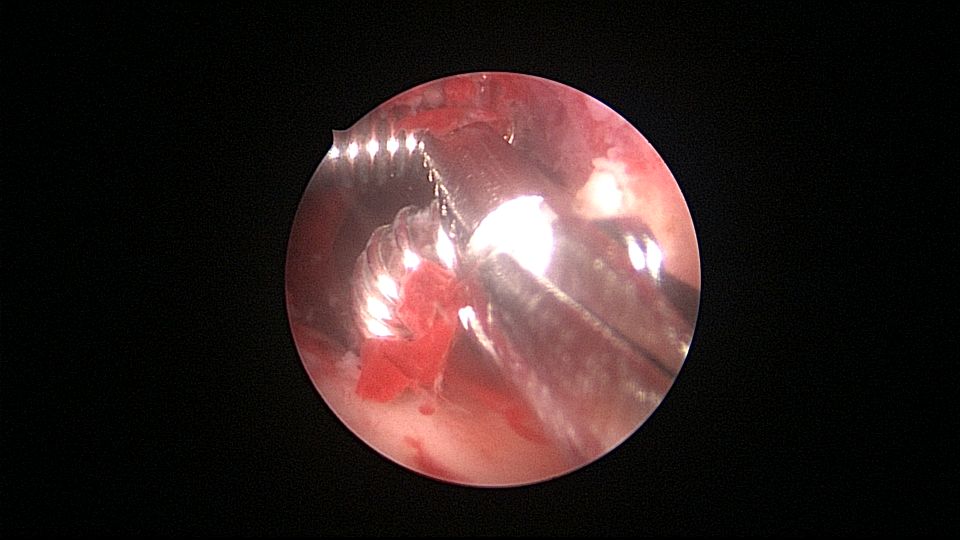

患者55岁,G1P1,顺产1次。安环31年,绝经3年,妇科检查发现宫颈外口息肉,B超宫腔未见分离暗区。子宫前位,宫腔镜见宫颈管下段多发息肉,宫颈内口粘连,宫腔少许淡黄色脓液流出,宫型环位置正常,被镜鞘推挤变形。助手单极电针切除宫颈管息肉时进针过深,引起较多出血,视野不清楚,接手手术,先止血、切除息肉,然后异物钳取出节育环,宫腔无其他异常。病检为宫颈管息肉。